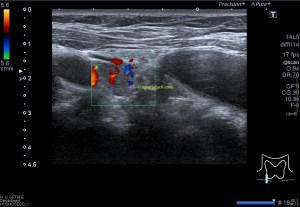

En la imagen 3 ves una imagen de un lipoma, mide 7 cms, la huella de la sonda mide 5cms, la «panoramic view» posee una regla centimetrada que sigue el contorno de la imagen, justo en la profundidad de la misma y lo marca la flecha amarilla. La profundidad la marca la flecha roja y la flecha blanca marca el rango centimetral de los 5cms, fíjate que la línea blanca es ligeramente mayor cada 5 cms. Sirve de referencia, como en la imagen 4 donde ves una colección en el glúteo de más de 10 cms.